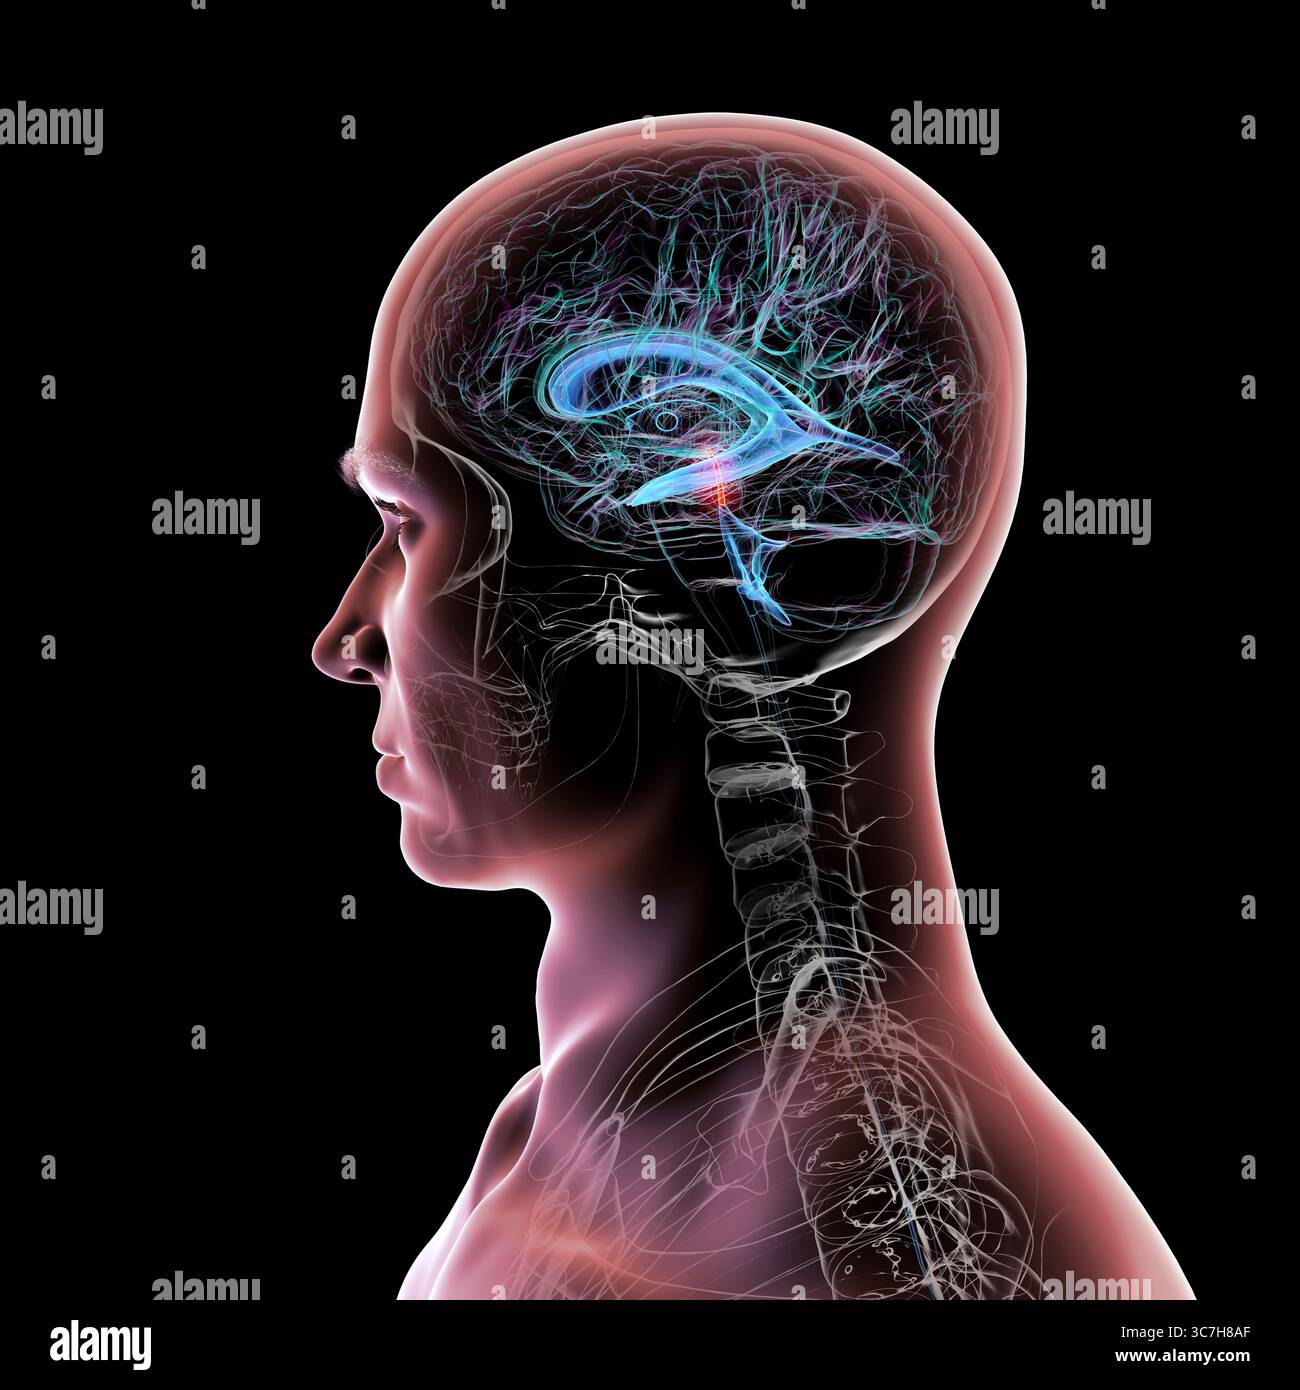

RF3C7H8A6–Abbildung des Gehirns mit hervorgehobenem Aquädukt (rot) und ventrikulärem System (blau), Darstellung des Liquorflusses.

RF3C7H8AA–Abbildung des Gehirns mit hervorgehobenem Aquädukt (rot) und ventrikulärem System (blau), Darstellung des Liquorflusses.

RF3C7H8AF–Abbildung des Gehirns mit hervorgehobenem Aquädukt (rot) und ventrikulärem System (blau), Darstellung des Liquorflusses.

RF3C7H8A3–Abbildung des Gehirns mit hervorgehobenem Aquädukt (rot) und ventrikulärem System (blau), Darstellung des Liquorflusses.